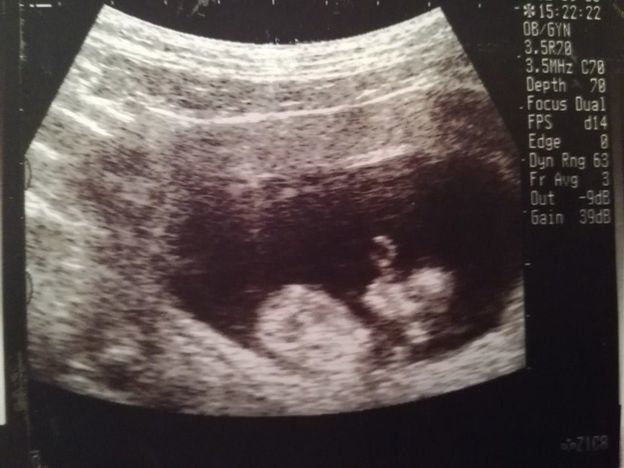

妊娠12週目のエコー写真

上の二つの画像は、同じ日に撮ってもらったもの。人の形になっている赤ちゃんの姿を確認して、体に衝撃が走りました。エコー画像上で、小さい体をモゾモゾと動かしている様子も見られて、本当にかわいらしく、感動して少し目が潤んでしまいました。人の姿として確認できる画像でしたので、夫に見せても、実家に帰省して両親に見せても、みんな「おぉー!」と喜びの声を上げていました。